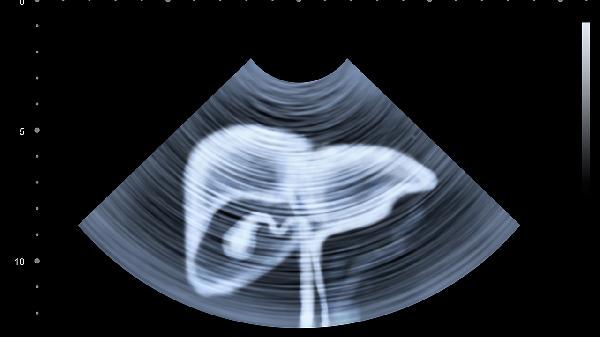

肝硬化或恶性肿瘤引起的腹水会使腹部均匀膨隆,叩诊呈浊音。移动性浊音阳性是典型体征,需通过腹腔穿刺明确性质。治疗需限制钠盐摄入,必要时行腹腔穿刺引流,同时针对原发病治疗。